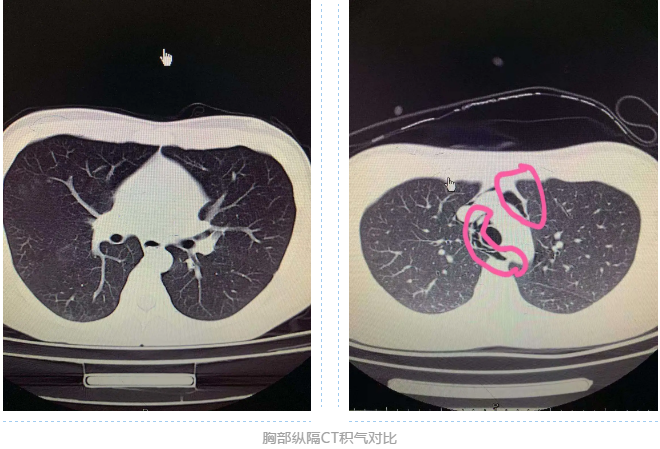

接诊后,顾梅凤医师帮小李进行了常规检查及喉镜检查,咽喉部没有找到异物。随后,又进行了颈部及胸部CT 检查,结果显示:食管周围上端、纵膈、心包内都有积气,食管管腔内外及颈部未见异物,考虑为食道穿孔,就这样,小李住进了医院。住院后,顾医师针对其病症,进行了下胃管,消炎,抑制胃酸、补液等对症治疗,并进行鼻饲管饮食,让小李不再做吞咽动作,有效预防感染。

经过一段时间治疗,复查胸部CT和颈部CT,看到积气吸收消失,经过试吃食物,没有任何不适感,于近日出院。